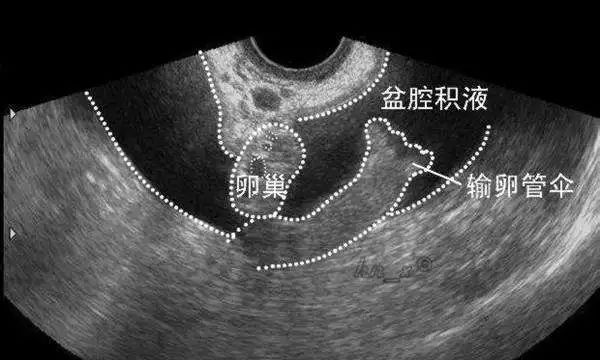

通常情况下,盆腔积液是看不到摸不着的,只有通过B超检查才能发现。

还有一种可能,卵巢每个月会有一枚卵泡发育成熟,并排出卵子。排卵的同时,卵泡液也会跟着流出来,就积在后陷凹里。所以,排卵后也常常会检查到盆腔积液。

划重点:平时我们看到的B超报告提示盆腔积液10-30mm,绝大多数是没有问题的。这就是一生理现象,不需要治疗。